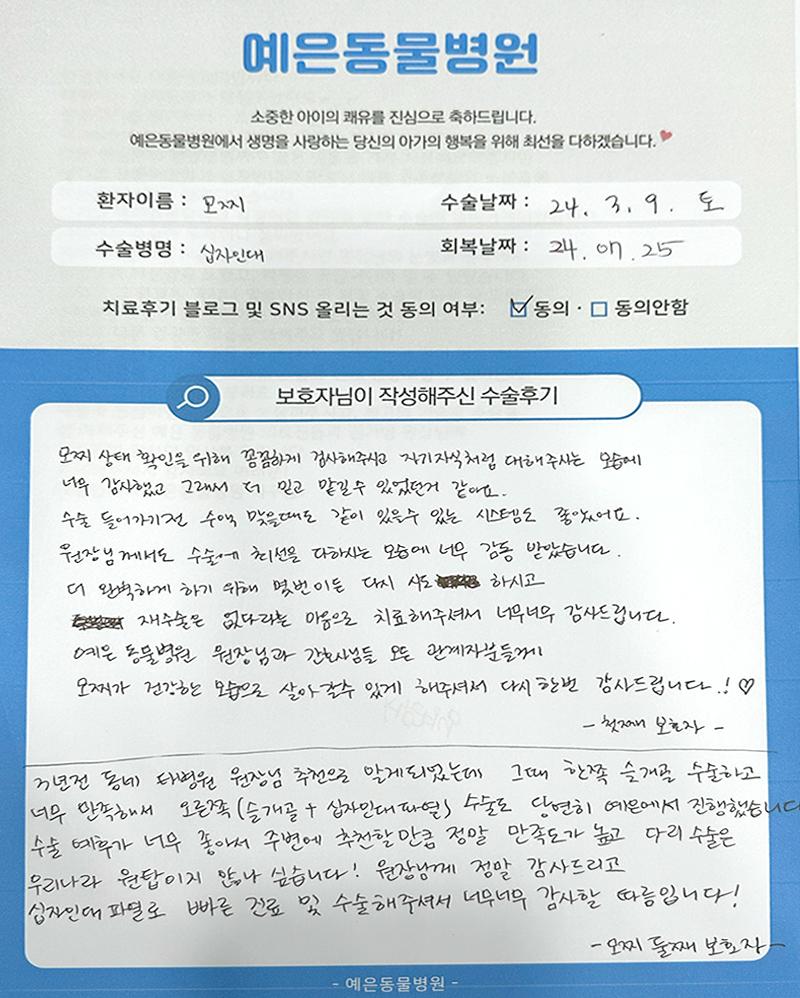

직접 작성해주신

정형외과 수술 후기 모음

돋보기를 눌러 크게 확인해보세요.

보호자님들이

직접 작성해주신

정형외과 수술 후기 모음

돋보기를 눌러 크게 확인해보세요.